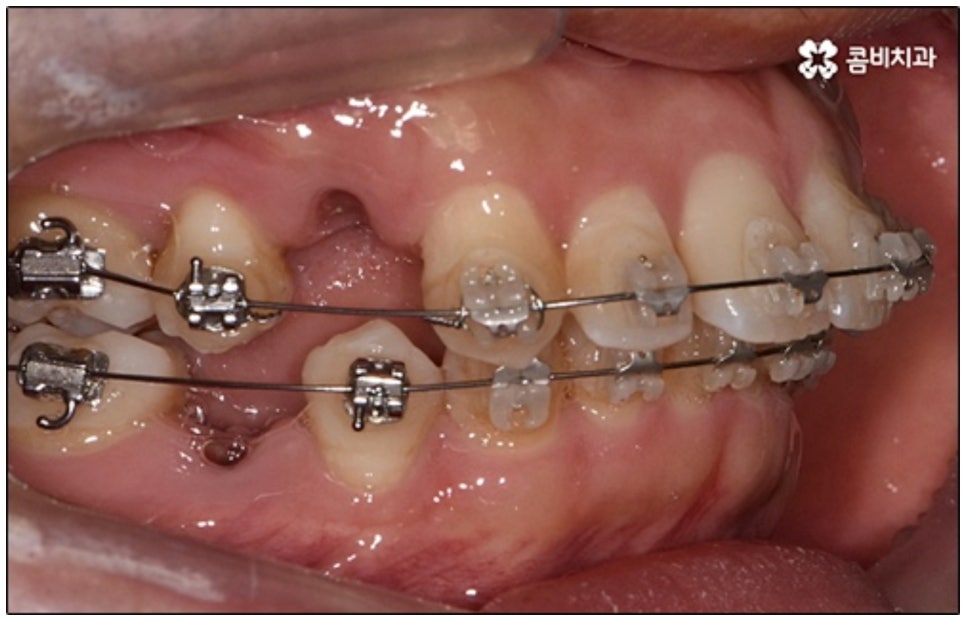

요즘 가장 많이 쓰이는 것은 클리피씨교정 장치로, 브라켓에 자체적으로 여닫을 수 있는 클립(뚜껑)이 있어 보다 손쉽게 와이어를 장착하거나 제거할 수 있어요. 이와 같은 자가 결찰 방식을 이용하게 되면 미세 철사로 일일이 와이어를 잡아주지 않아도 되기 때문에 장치로 인한 불편함이나 통증이 줄어들 수 있는데요. 뿐만 아니라 관리를 위해 치과에 내원하여 진행 상황에 맞게 새로운 와이어로 교체하고 교정력을 걸어주는 데 걸리는 시간 역시 단축되며, 상황에 따라 내원 횟수 자체를 줄여줄 수도 있어 방문 시간을 내는 것이 자유롭지 않은 군인분들이나 직장인분들도 치료할 수 있어요.

또한 클리피씨교정 장치는 심미성이 높기 때문에 많은 분들이 선호하고 있는데요. 클립이 달린 세라믹 (cilppyC-Ceramic의 약자) 이라는 뜻을 가진 이름에서 알 수 있듯이 클리피씨교정 장치는 브라켓 소재가 치아 색상과 비슷하여 눈에 잘 띄지 않으며 내구성이 좋고 크게 변색 되지 않는다는 장점을 가지고 있어요.

말씀드린 것과 같은 다양한 이점들이 있기 때문에 현재 본원의 교정 환자분들은 대부분 클리피씨교정 장치를 이용하여 치료를 진행하고 있습니다. 사진 역시 돌출입 교정을 위해 발치 후 클리피씨교정 장치를 이용하신 환자분의 케이스인데 시간이 지날수록 점차 앞니가 자연스럽게 들어가고 위아래 교합이 정확하게 맞아가는 것을 확인하실 수 있을 거예요.